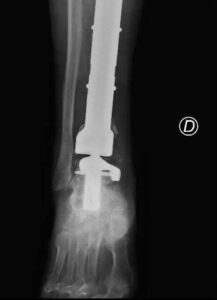

(Adnkronos) - Una protesi di caviglia costruita su misura salva la gamba bionica di Mario, paziente 80enne protagonista di un...